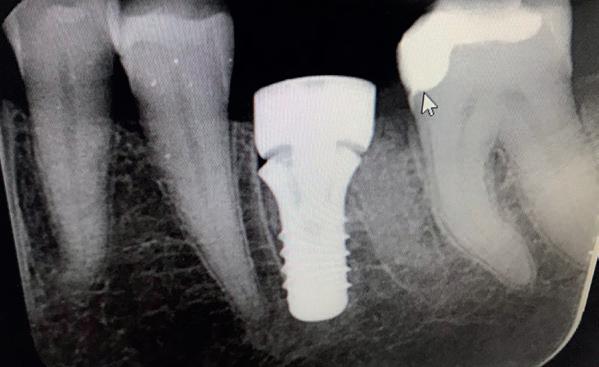

Casus

In deze casus is extractie van de 37 geïndiceerd in verband met een fistel en restpockets, zoals zichtbaar op de röntgenfoto’s (afbeelding 1). Duidelijk te zien is de forse peri-apicale ontsteking en het botverlies bij de 37, dat zowel richting buccaal als linguaal doorloopt. De 37 wordt atraumatisch verwijderd. Er is aan de linguale zijde veel bot verloren en er is sprake van een perforatie aan de buccale zijde.

Er wordt besloten om botmateriaal te plaatsen in de extractie-alveole. Vervolgens wordt het afgesloten met een titanium versterkt d-PTFE membraan (afbeelding 2). Na vier weken wordt het membraan verwijderd.

Zes maanden na extractie wordt het implantaat 37 geplaatst. Er is sprake van een goede genezing en de processushoogte en -breedte zijn behouden en opgebouwd. Ook is er zichtbaar gekeratiniseerd weefsel

gewonnen. De wond kan na het plaatsen van een healing abutment primair gesloten worden (Afbeelding 3a-3d).

In afbeeldingen 4a-c is het resultaat drie maanden na het plaatsen van het implantaat te zien. De genezing is volledig en de verwijzer kan de suprastructuur vervaardigen (afbeelding 4a-4c).

In afbeeldingen 5a-d is de implantaatkroon 37 te zien, twee jaar na plaatsing. Op de röntgenfoto is herstel van zowel corticaal als spongieus bot te zien. (De CB-CT was vervaardigd in verband met implantologische indicatie in het naastliggende gebied).